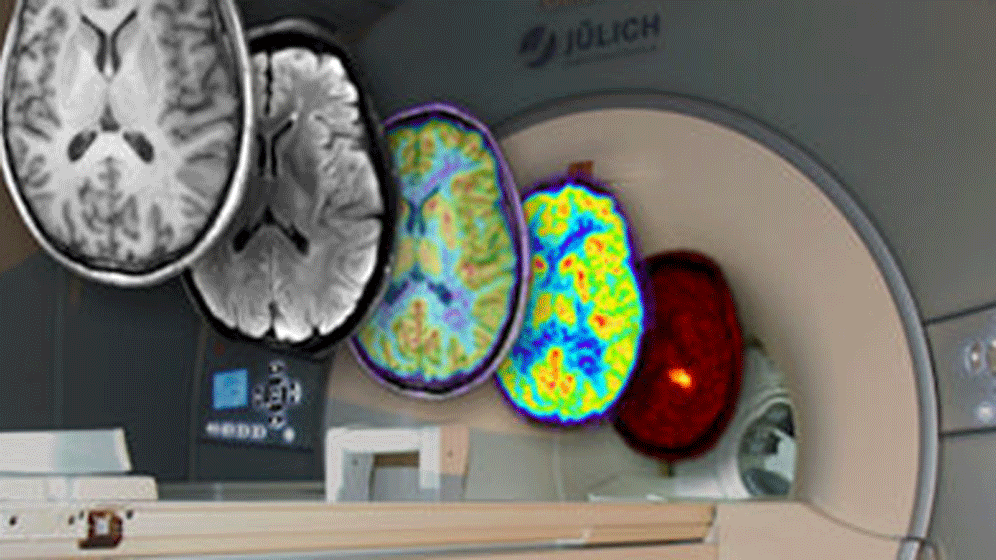

Mit der in den 1990ern entwickelten funktionellen Magnetresonanztomographie (fMRT) können Wissenschaftler die Gehirnaktivität eines Probanden verfolgen, während dieser im MRT-Scanner eine Aufgabe ausführt oder auf Reize reagiert. Bis heute ist das Verfahren in Tausenden Studien eingesetzt worden, um den „Sitz“ der unterschiedlichsten Verhaltensfunktionen im Gehirn zu bestimmen. Fachsprachlich spricht man von „behavioralen Funktionen“.

Jülicher und Düsseldorfer Hirnforscher machen sich nun für einen neuen Ansatz stark und empfehlen dabei im Kern eine Umkehrung der bisherigen Praxis: Statt mit vordefinierten Verhaltensfunktionen zu beginnen und diesen Gehirnregionen zuzuordnen, würde zunächst eine anatomisch definierte Hirnregion ausgewählt. Auf Basis eines weitreichenden statistischen Screenings nach möglichen behavioralen Verbindungen, würde dann ein „behaviorales Profil“ gewonnen.

Möglich wird ein solcher „Bottom-up“-Ansatz durch seit kurzem etablierte Datenbanken für neurowissenschaftliche Bildgebungsstudien, in denen die gewonnenen Daten aus Tausenden Studien verfügbar gemacht werden und weiter analysiert werden können. Metaanalysen dieses Datenreichtums, argumentieren die Autoren, könnten „Kernfunktionen“ der Areale enthüllen, die in den einzelnen Studien nicht sichtbar werden.